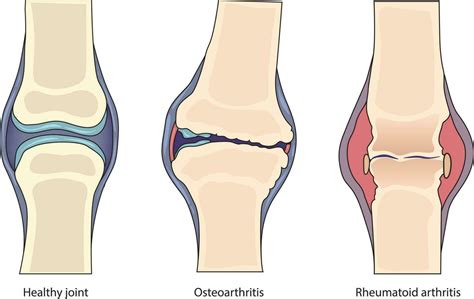

Además de factores de riesgo evidentes como la edad avanzada (mayor de 60 años) y bacteriemia reciente, diversas condiciones médicas predisponen a infecciones articulares no gonocócicas. Entre las más comunes se encuentran la enfermedad articular degenerativa, la artritis reumatoide y la terapia con corticosteroides. Los pacientes con artritis reumatoide presentan una incidencia de artritis séptica aproximadamente un 10% mayor que la población general.

Las enzimas bacterianas, sus toxinas, los radicales libres y las enzimas lisosomales liberadas por los neutrófilos del huésped contribuyen a la destrucción del cartílago. Las citocinas activan las metaloproteasas de la matriz, que también participan en la autodigestión del cartílago. La isquemia, provocada por la acumulación de exudado purulento que aumenta la presión intraarticular y disminuye el flujo sanguíneo sinovial, conduce a la anoxia del cartílago.